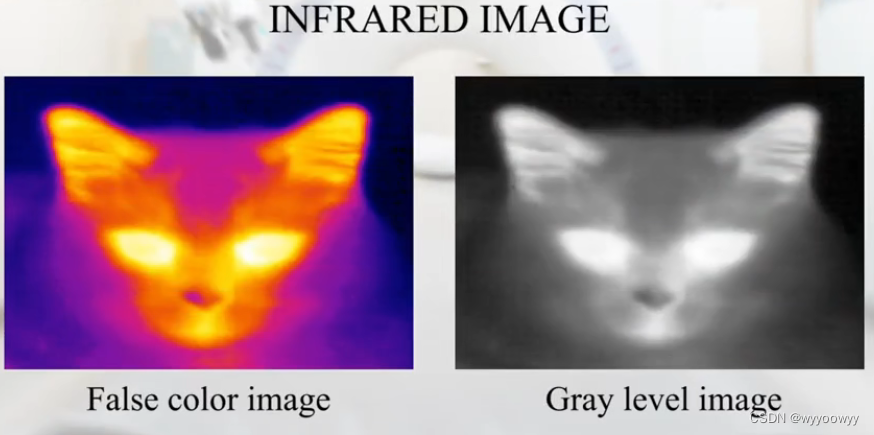

8、医学图像的类别

两个灰度值:比如0/1,0/255

多个灰度值,比如0-255

彩色图像:三个灰度图像的叠加 RGB,三个channel

红外图片,能够很好地表达温度的变化